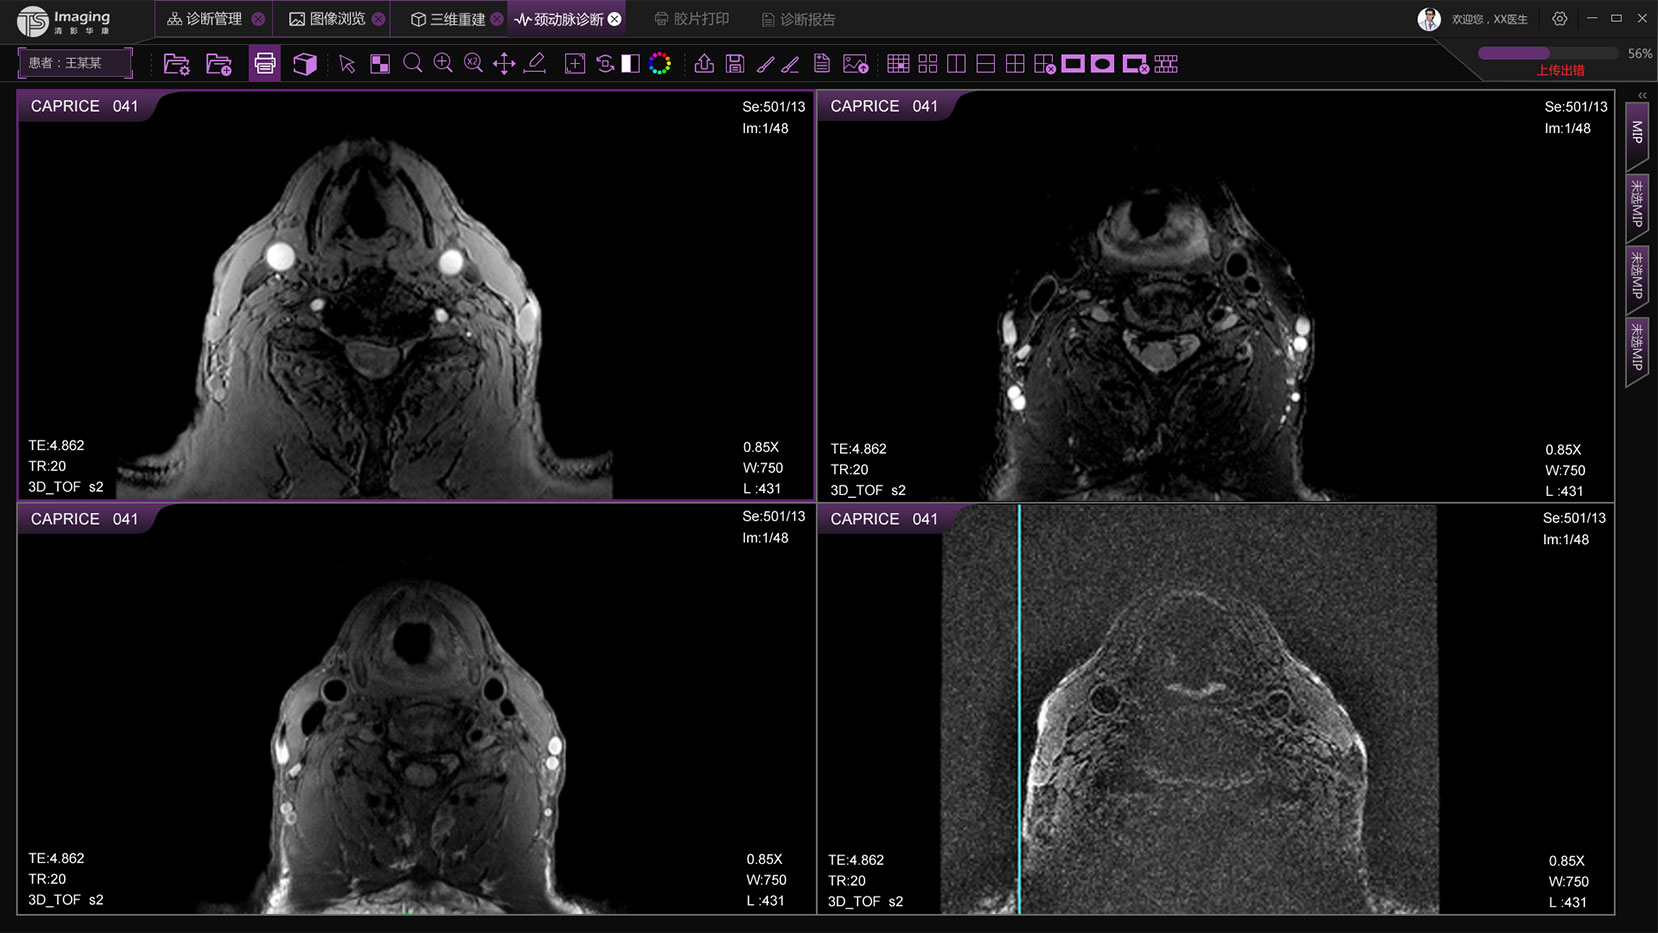

頸動脈診斷頁面

頸動脈診斷頁面整體布局和三維重建比較相似,最大的區別是右側的操作區域,血管分析都為按鍵操作,通過間隔的大小分成三部分。單層切片除了按鍵還有下拉菜單的操作。

頸動脈診斷原型